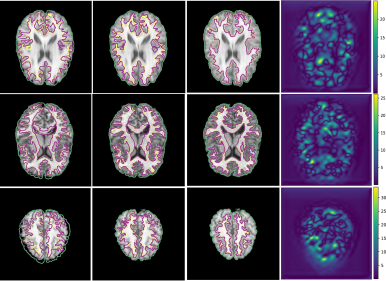

Refer to caption

Figure 4: Visual validation of proposed Conv2Warp method on brain dataset. 1stsuperscript1𝑠𝑡1^{st} column: Target image with source mask, 2ndsuperscript2𝑛𝑑2^{nd} column: target image with deformed (transformed) mask, 3rdsuperscript3𝑟𝑑3^{rd} column: Target image with target mask, and last column: magnitude of predicted deformation field. Grey matter (GM) and white-matter (WM) areas are marked by green and magenta borders and yellow borders, respectively.

In Fig. 3 Conv2Warp without (λ=0𝜆0\lambda=0) regularization and with (λ=0.001𝜆0.001\lambda=0.001) regularization are shown in 4th and 5th columns respectively and their corresponding DVF magnitudes in 6th and 7th columns, respectively. It can be observed that the unconstrained loss function results in some unrealistic deformations (red rectangular regions in 4th column) while a more realistic deformations are visible for the constrained loss proposed in Conv2Warp (5th column). A smooth deformation can be seen in the magnitude image of the DVF uregdelimited-∣∣subscriptu𝑟𝑒𝑔\mid\textbf{u}_{reg}\mid (7th column). Colour overlay images show a large improvement in the alignment of source images Issuperscript𝐼𝑠I^{s} with the target images Itsuperscript𝐼𝑡I^{t} (3rd column) with Conv2Warp method (5th column). Fig. 4 shows the results on T1 MRI test datasets which were first rigidly aligned to MNIspace and then co-registered using Conv2Warp. It can be observed that Conv2Warp handles different magnitudes of non-linear deformations.